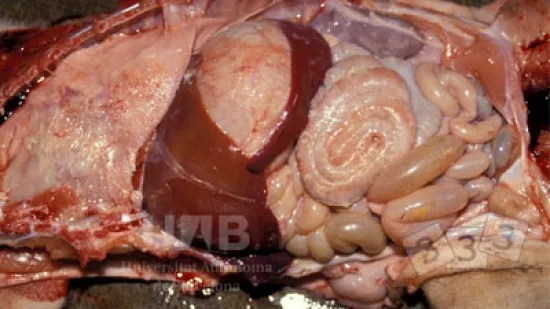

Semaine du 10-Mai-2021

Quelle maladie peut produire cette lèsion ?